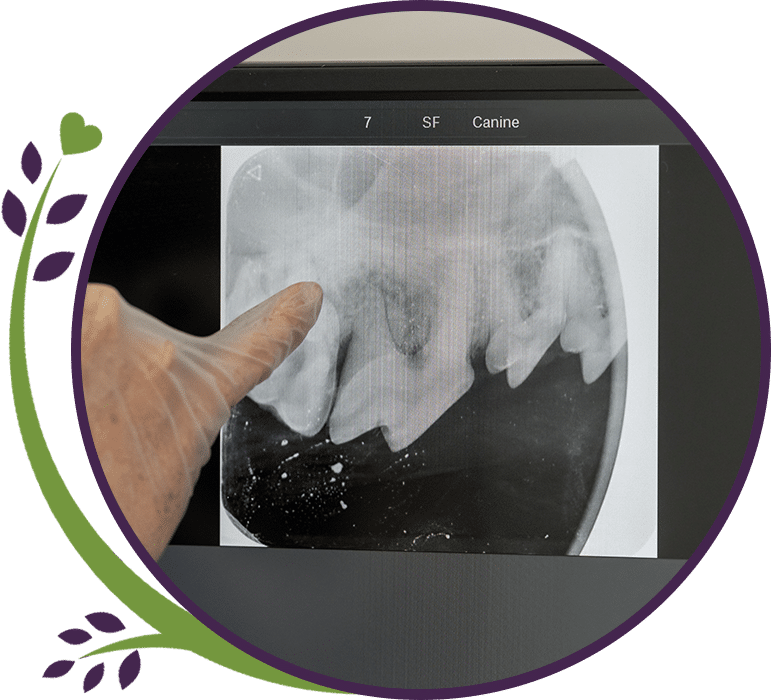

Why We Do Dental Radiographs

Dental radiographs are a crucial part of comprehensive veterinary dental care. Many dental problems in cats and dogs occur beneath the gumline, where they cannot be seen during an exam. Radiographs allow us to detect issues such as:

- Root fractures

- Abscesses or infections

- Painful resorptive lesions in cats